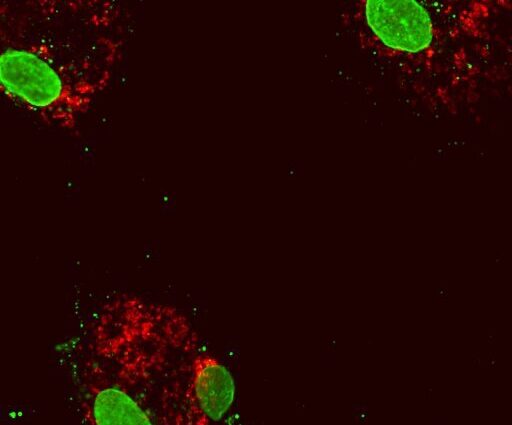

I team hanno applicato strumenti di ingegneria genetica e imaging cellulare per esaminare le cellule di persone con cellule normali, quelle con mutazioni di perdita di funzione nell’espressione di DNMT3A o TET2 e quelle con aterosclerosi.

Sorprendentemente, bassi livelli di espressione di DNMT3A e TET2 nelle cellule del sangue portano a una ridotta espressione di TFAM, che a sua volta porta a un imballaggio anormale del DNA dei mitocondri, istigando l’infiammazione a causa del DNA mitocondriale rilasciato.

”Abbiamo scoperto che le mutazioni DNMT3A e TET2 impediscono la loro capacità di legare e attivare il gene TFAM”, afferma il primo autore Isidoro Cobo, ricercatore post-dottorato nel laboratorio Glass dell’UC San Diego. “La mancanza o la riduzione di questa attività di legame porta al rilascio di DNA mitocondriale e a una risposta iperattiva all’infiammazione mitocondriale, e crediamo che questo possa esacerbare l’accumulo di placca nell’aterosclerosi”.

Crediti: Isidoro Cobo of UC San Diego